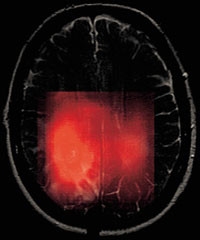

I flervolumteknikker blir en serie med data registrert fra en rekke volumer i samme opptak. Disse teknikkene kalles med en fellesbetegnelse kjemisk skift-avbildning eller metabolsk bildedanning (Chemical Shift Imaging, CSI). For utredninger i forbindelse med patologiske forhold i hjernen kan det typisk registreres fra 8 ¥ 8 til 32 ¥ 32 spektre. Snittene er vanligvis tykke (1 – 2 cm) for å oppnå godt nok signal-til-støy-forhold. Oftest visualiseres CSI-data ved at intensiteten av en enkelt metabolitt i spekteret fremstilles i en gråtoneskala hvor høyt metabolittnivå gir mest intenst signal. Gråtoneintensiteten fra alle spektrene gir et metabolittbilde. Dette korreleres til et MRI-bilde ved å legge disse oppå hverandre. MR-bilder kan brukes for å anslå mengden av de forskjellige vevstyper (f.eks. grå og hvit hjernesubstans) innenfor et volum (segmentering), for deretter å korrigere for antatt mengde av de forskjellige typene av vev (2). Dette er spesielt viktig i studier hvor det er små forskjeller i metabolittkonsentrasjon mellom en normal og en patologisk tilstand.

In vivo-MRS-observasjoner av endret metabolisme kan være nyttig f.eks. for å bestemme hvor overgangen går mellom kreftvev og normalt vev, og for å skille mellom arrvev etter operasjon og strålebehandling fra tilvekst av nytt kreftvev (8). Ett av de viktigste områdene for bruk av MRS vil være oppfølging av pasienter der det er spørsmål om tumorresidiv. Klassifisering av svulstene er til en viss grad mulig ved hjelp av in vivo-MR-spektroskopi i kombinasjon med avansert dataanalyse (9, 10). Et eksempel på et CSI-bilde av kolin er vist i figur 4. Det forhøyede kolinnivået stemmer overens med tumorområdet i MR-bildet.